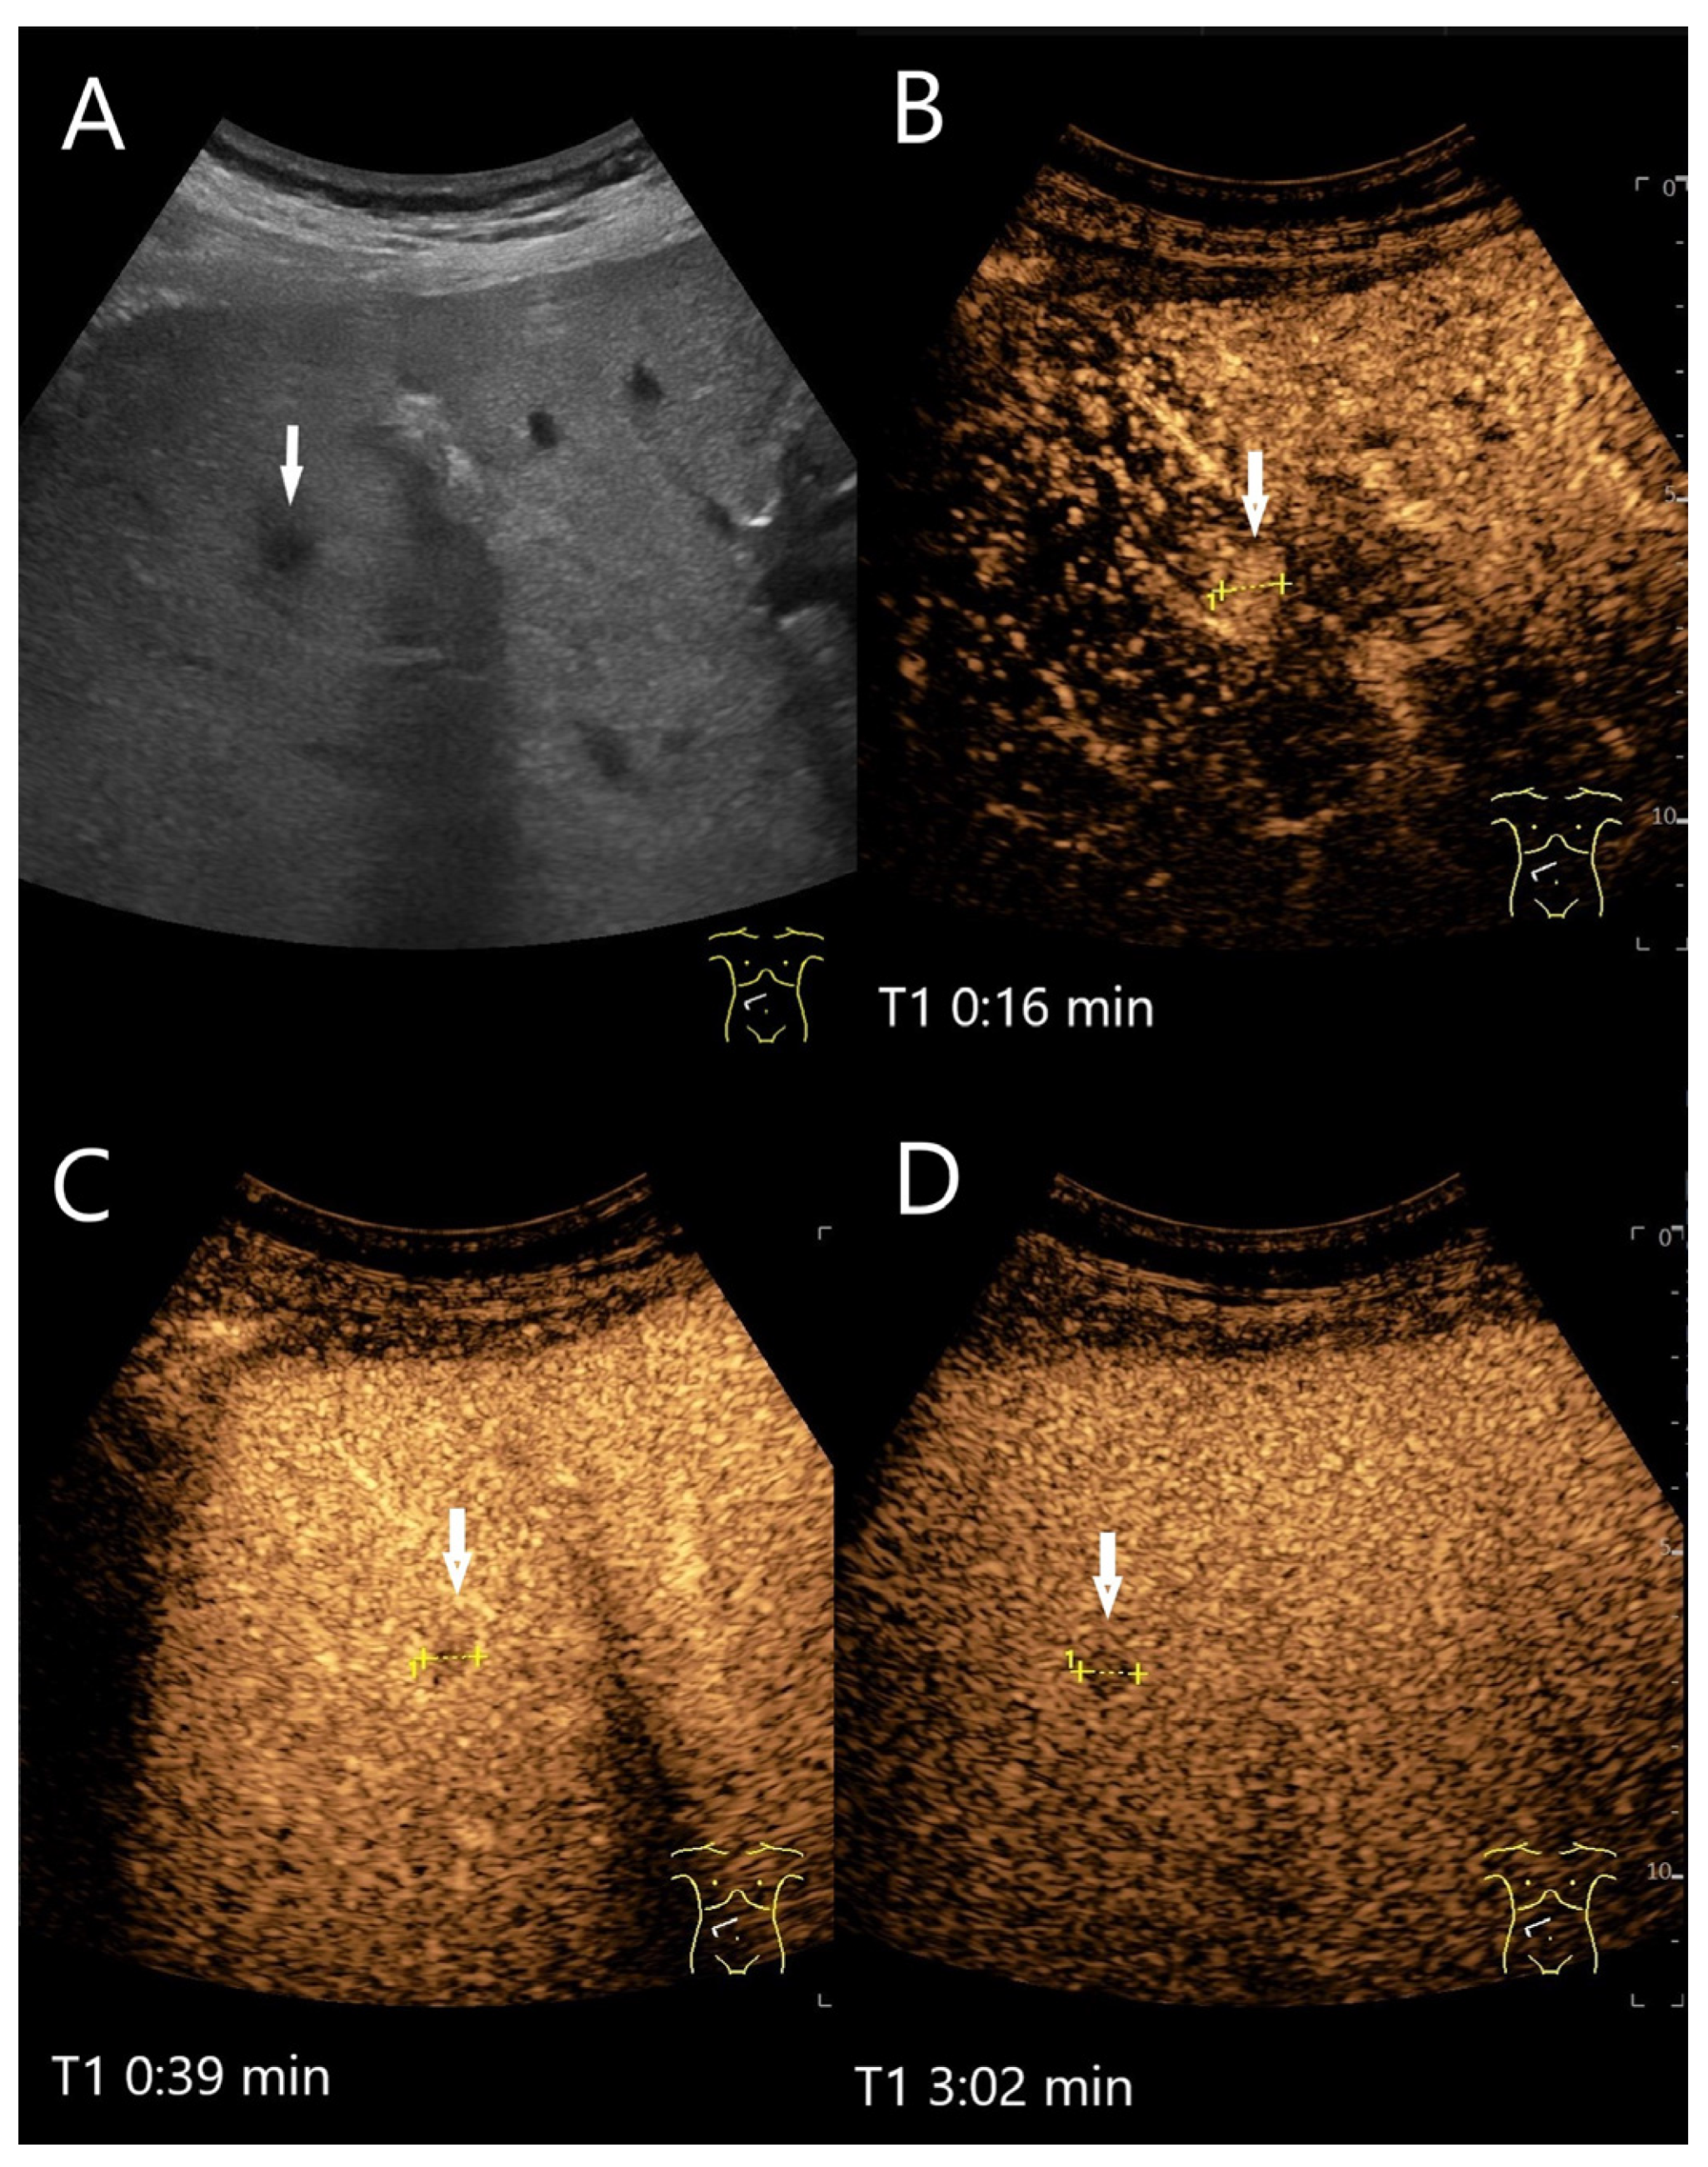

Figure 9.

Chronic pyogenic liver abscess. Patient with hypoechoic lesion (arrow) with high inflammatory laboratory (A). CEUS shows mild arterial hyperenhancement after 16 s (B), with mild washout after 1 min (C) and progressive washout after 3 min (D). The US-guided biopsy revealed the histologic diagnosis of a chronic granulocytic sclerosing inflammation.